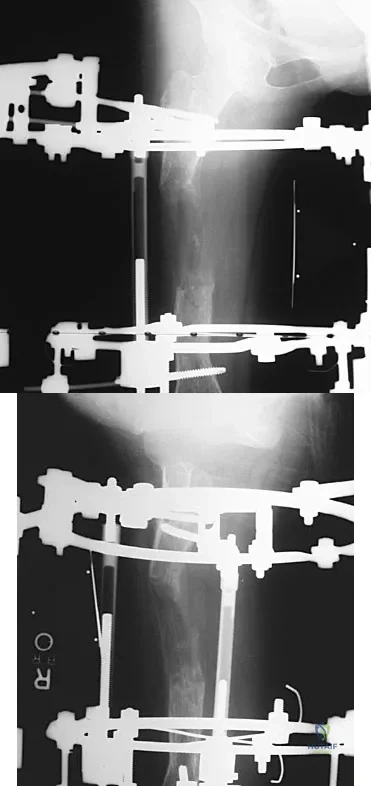

Figures 45a and 45b show the AP and lateral radiographs of a 15-year old patient who is undergoing surgery to add 3 cm of length to the femur. Based on the radiographic findings, what is the next most appropriate step in management?